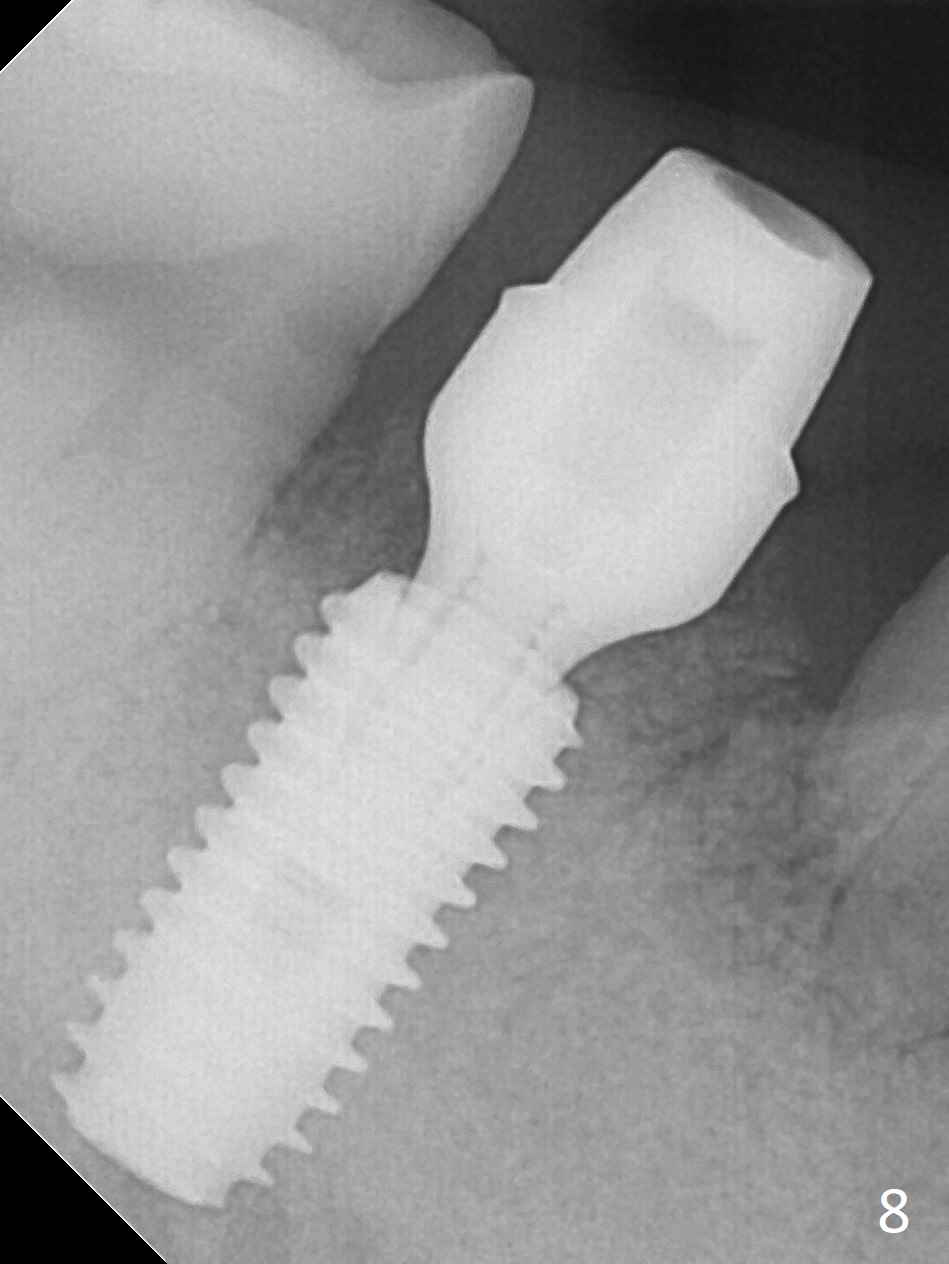

Although the tooth #30 has distobuccal root exposure (Fig.1 <), it is asymptomatic. In contrast the tooth #31 with the distoocclusal caries (*) is symptomatic. After use of 2 mm drill for 18 mm (lingual gingival margin), a calculated parallel pin is inserted (Fig.2 (D: 2 distal roots of the tooth #30)). It appears that a 11.5 mm long implant is appropriate for the site; a 5 mm cuff is expected. Following 4.8 mm drill, a 5.5x11.5 mm implant is placed initially (Fig.3) with an apical space (*) and clearance from the Inferior Alveolar Canal (red dashed line). The implant is placed deeper with placement of a 6.5x4(5) mm abutment and bone graft (*, Fig.4,5). After placement of collagen membrane over the graft, an immediate provisional is fabricated (Fig.6 P) with clearance from the opposing tooth (Fig.7 *). There is no bone loss 3.5 months postop (Fig.8). In fact the abutment has not been seated completely since its placement (Fig.4,5,8). The crown/abutment dislodges 3 years 3 months post cementation (Fig.9). The latter occurs for long incubation time because of opposing partial denture (Fig.10). After trimming proximal surfaces (Fig.11: arrowheads), the abutment remains incompletely seated (Fig.11) due to possible crestal bone interference (Fig.11 *). The smaller abutment by itself remains unseated (Fgi.12). One size small one is completely seated (Fig.13). Impression is taken. Two weeks later the abutment margin is supragingival. After screw torque at 20 Ncm, the crown is cemented with access hole. Excess cement is removed.